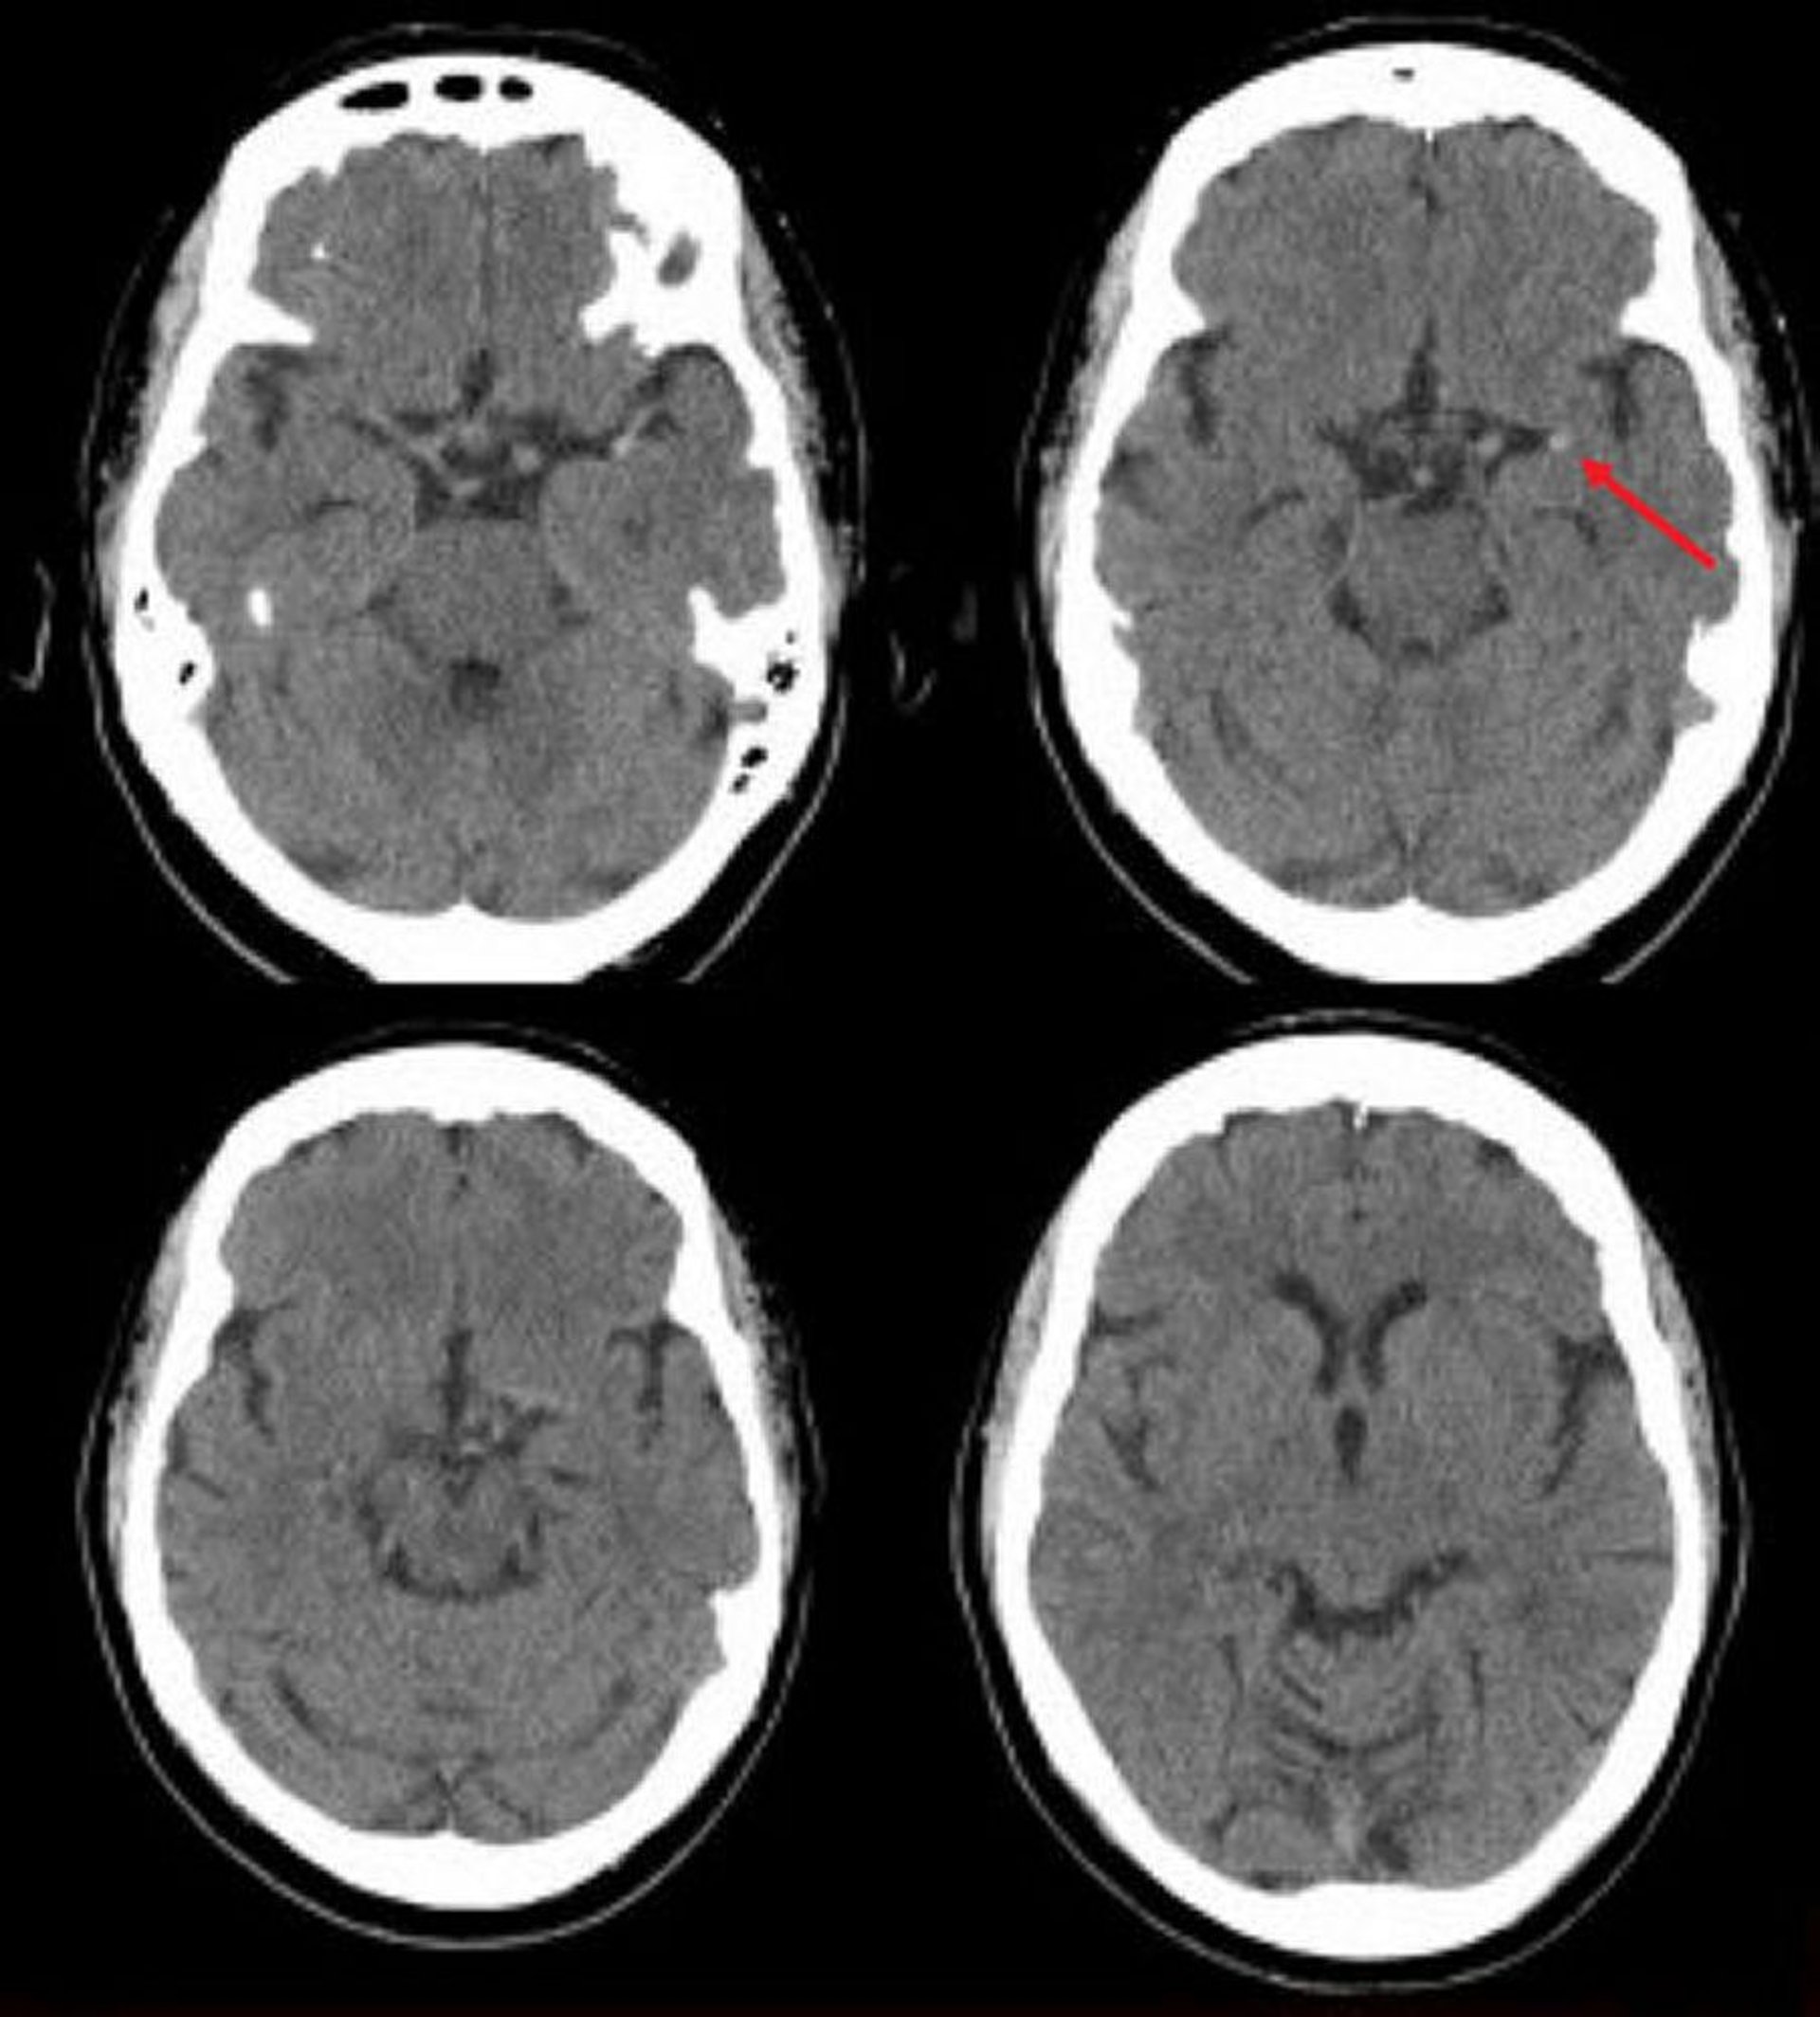

Accident vasculaire cérébral ischémique de l'artère cérébrale moyenne gauche (TDM)

Cette TDM de la tête sans contraste montre une artère cérébrale moyenne gauche hyperdense. Ce signe indique un caillot focal dans l'artère cérébrale moyenne gauche (flèche).

Image courtoisie de Ji Y. Chong, MD.